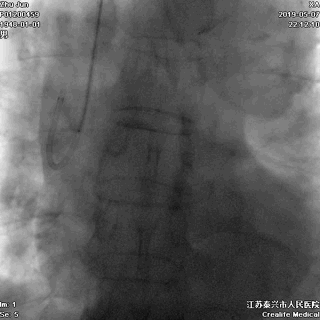

胸部X-线透视,掌握患者更多基础信息